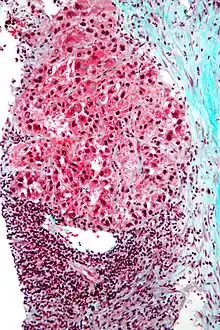

Additional images